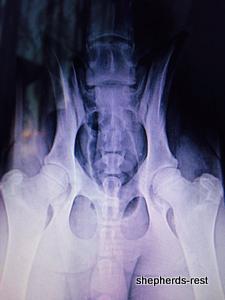

Sırtlan's hip x-rays in Turkey July 2014